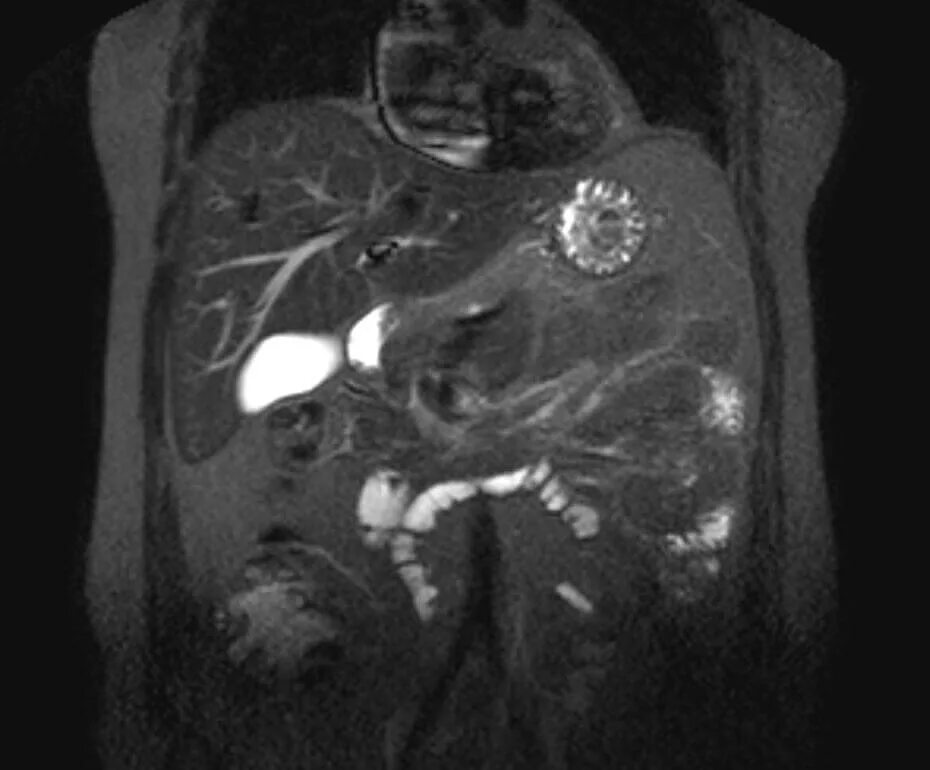

Что проверяет мрт брюшной полости